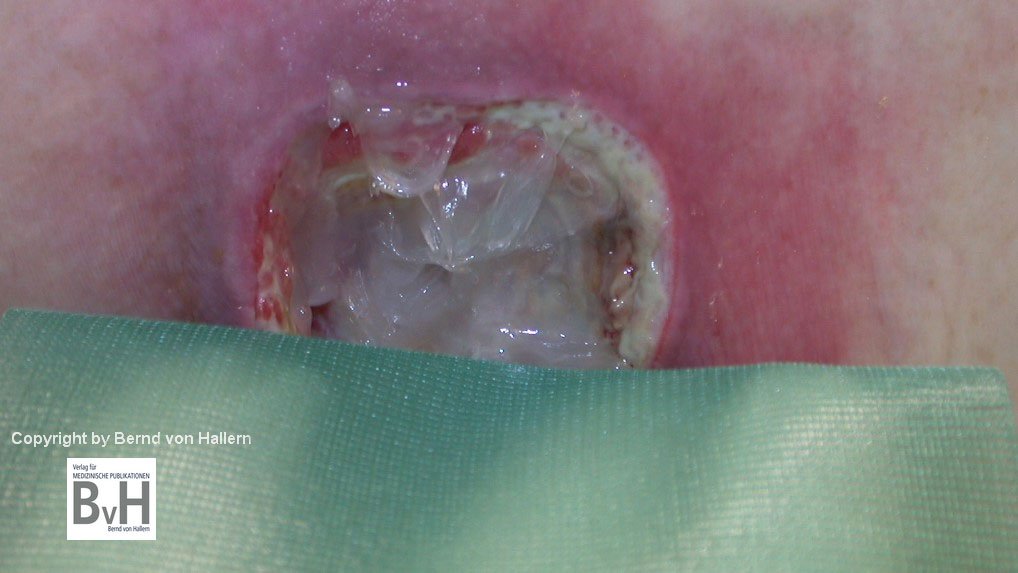

Schädlich für die Wundheilung, besser nicht benutzen

Bild 1: Spülung eines Amputationsstumpfes mit H2O2. Die Lösung schäumt auf.

Bild 2: Granulierender sakraler Dekubitus, keine Infektion, vor Spülung mit H2O2.

Bild 3: Nach H2O2- Spülung zeigt sich ein weißer Wundgrund durch oxidierte Zellen.